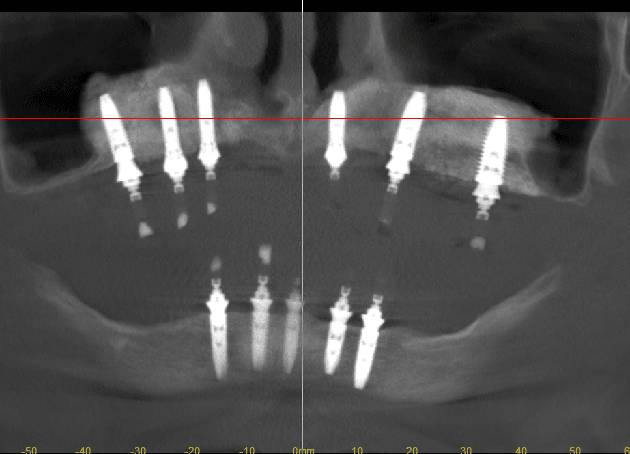

Ez itt egy 2 éve befejezett csontpótlással megoldott eset, egy 68 éves hölgyé. A valahol beültetett összes felső implantátumát el kellett távolítani, hatalmas csonthiányok… Helyére óriási csontpótlások…majd beültettünk felülre 6, alulra 5 db implantátumot.

4 műtét, 18 hónapnyi kezelés.